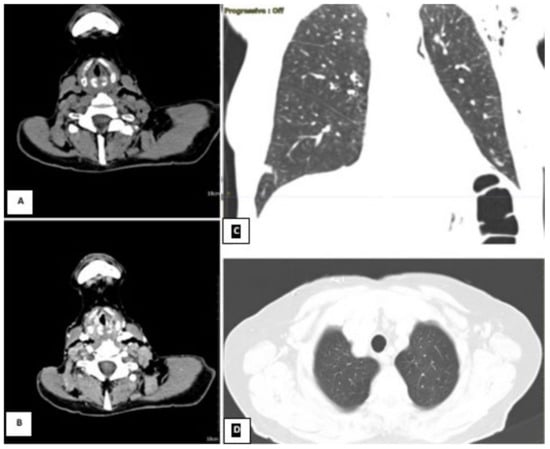

Figure 2.

CT scan showing (during hospitalization) pneumonia by Cytomegalovirus. At the lateral-basal segment of the right inferior lobe, in the subpleural level, the gross intraparenchymal collection with hydro-aerial content is compatible with the pneumatocele. In the lung window, multiple areas of parenchymal thickening are visible in the right basal location. (On the left, coronal section parenchymal window, on the right, axial section lung window). Partial laryngectomy (OPHL II B) with bilateral selective neck dissection (cervical nodal Robbins levels II–IV) and postoperative radiotherapy were planned to manage this case. Unfortunately, this planned surgical intervention was impossible because of the patient’s poor general conditions. Moreover, one of the follow-up CT scans of the chest (three months after the initial one) revealed the presence of bilateral diffuse multiple micronodules, which were considered early distant metastasis from the laryngeal adenoid cystic cancer (Figure 3).

Figure 3.

CT scan windows showing metastasis and inflammatory phenomena on both sides of the lung. (On the left, axial parenchymal lung section. On the right, axial lung window). During hospitalization, bacterial pneumonia began, worsened by secondary viral (Cytomegalovirus) and fungal pneumonia. The patient received a triple antibiotics course with an antiviral, an antifungal, and systemic and local inhalational corticosteroids. However, despite the medical therapy, the chest condition deteriorated progressively (Figure 4).